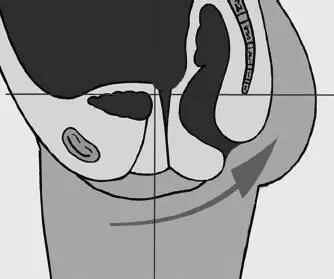

Чаще всего таз опрокидывается вперед своей верхней половиной – подвздошными костями. Это связано с тем, что при тяге «заднего костюмчика» вверх крестец ползет за ним, а лобок, соответственно, проворачивается за ним вниз. В результате вместе с лобком (лонной костью) опрокидываются вперед и вниз подвздошные кости таза, точь-в-точь как настоящий банный тазик.

Спереди при этом выпирает животик, вываливаясь вперед вслед за тазом. А сзади либо увеличивается гиперлордоз поясничного отдела (приводя к излишнему провалу в пояснице), либо (при спрямлении позвоночных изгибов) тяга позвоночника вверх волной идет по позвоночнику, «опрокидывая» вниз лицо, которое повторит движение таза (тем самым лишний раз подтверждая верность принципа «отзеркаливания» головы от таза).

Рис. 76. Отклонение таза вперед, крестец выше нормы